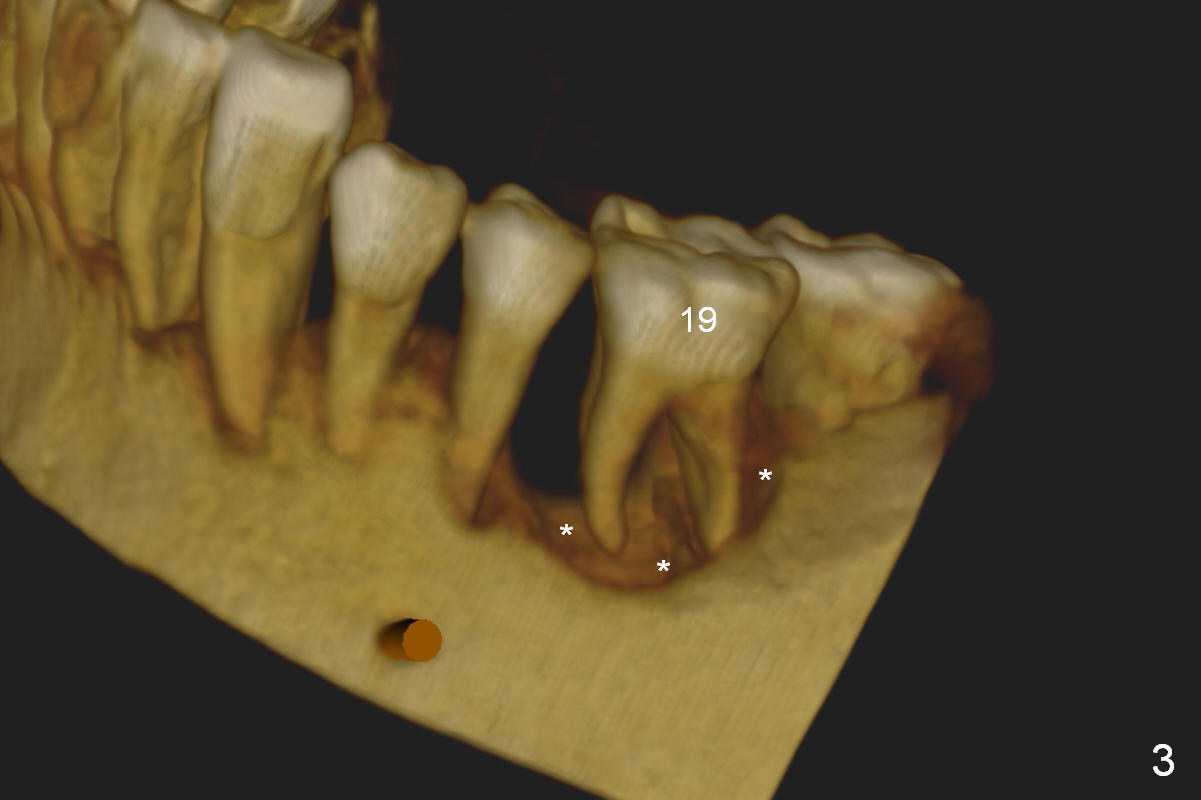

A 45-year-old man (SH) has periodontal (#3,9,19,23 (bone loss: Fig.1-3 *)) and orthodontic (#7,10 cross bite) problems, which he wants to solve at the same times. The tooth #19 is symptomatic (Fig.4,5). Infiltrate the buccal plate with 2% Xylocaine 1:50,000 Epinephrine and Septocaine (away from the Mental Foramen). After extraction and debridement, the socket is treated with Metronidazole. Osteotomy is initiated slightly buccal (B) to the middle of the socket bottom (Fig.5), using Sinus Master Kit drills (6 mm deep). After each drill, gently explore the lingual wall of the osteotomy with a fine curette or an explorer to determine whether the wall is perforated or not. Place a 5.5x13 mm implant (or short) between the buccal plate and the Inferior Alveolar Nerve (brown circle). If the torque is high, use the corresponding drill and tap. A 5.5 mm angled abutment will be used (15 or 25°, will arrive Monday morning). When X-ray is taken, the apex of the osteotomy should be superior to the upper border of the Inferior Alveolar Canal (Fig.4 U) and inferior to the Lower one (L). Bone graft is placed (Fig.4,5 red circles) after placement of PRF buccally (Fig.5 yellow curved line). If visibility is poor, make an incision and insert Epinephrine gauze under periosteum for hemostasis. Take photos when a 2 mm pilot drill in place to show the coronal end of the drill at the lingual cusp instead of the central fossa.